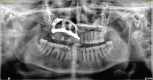

Rationale: The successful utilisation of three dimensional (3D) techniques in engineering a titanium patient specific implant (PSI) for a patient who underwent hemimaxillectomy following post COVID mucormycosis infection.

Diagnosis: The patient affected by mucormycosis was left with Aramany class 1 and Cordeiro type II sub total maxillectomy defect.

Treatment: The patient was operated for mucormycosis followed by reconstruction with patient specific implant.

Outcome: Positive clinical outcomes, including improved facial symmetry, function and psychological well being with immediate replacement of the teeth, the benefits of which far outweigh the traditional approach.